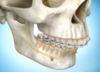

CAS COMPLEXES ET CHIRURGIE ORTHOGNATHIQUE

Chirurgie Bi-Maxillaire